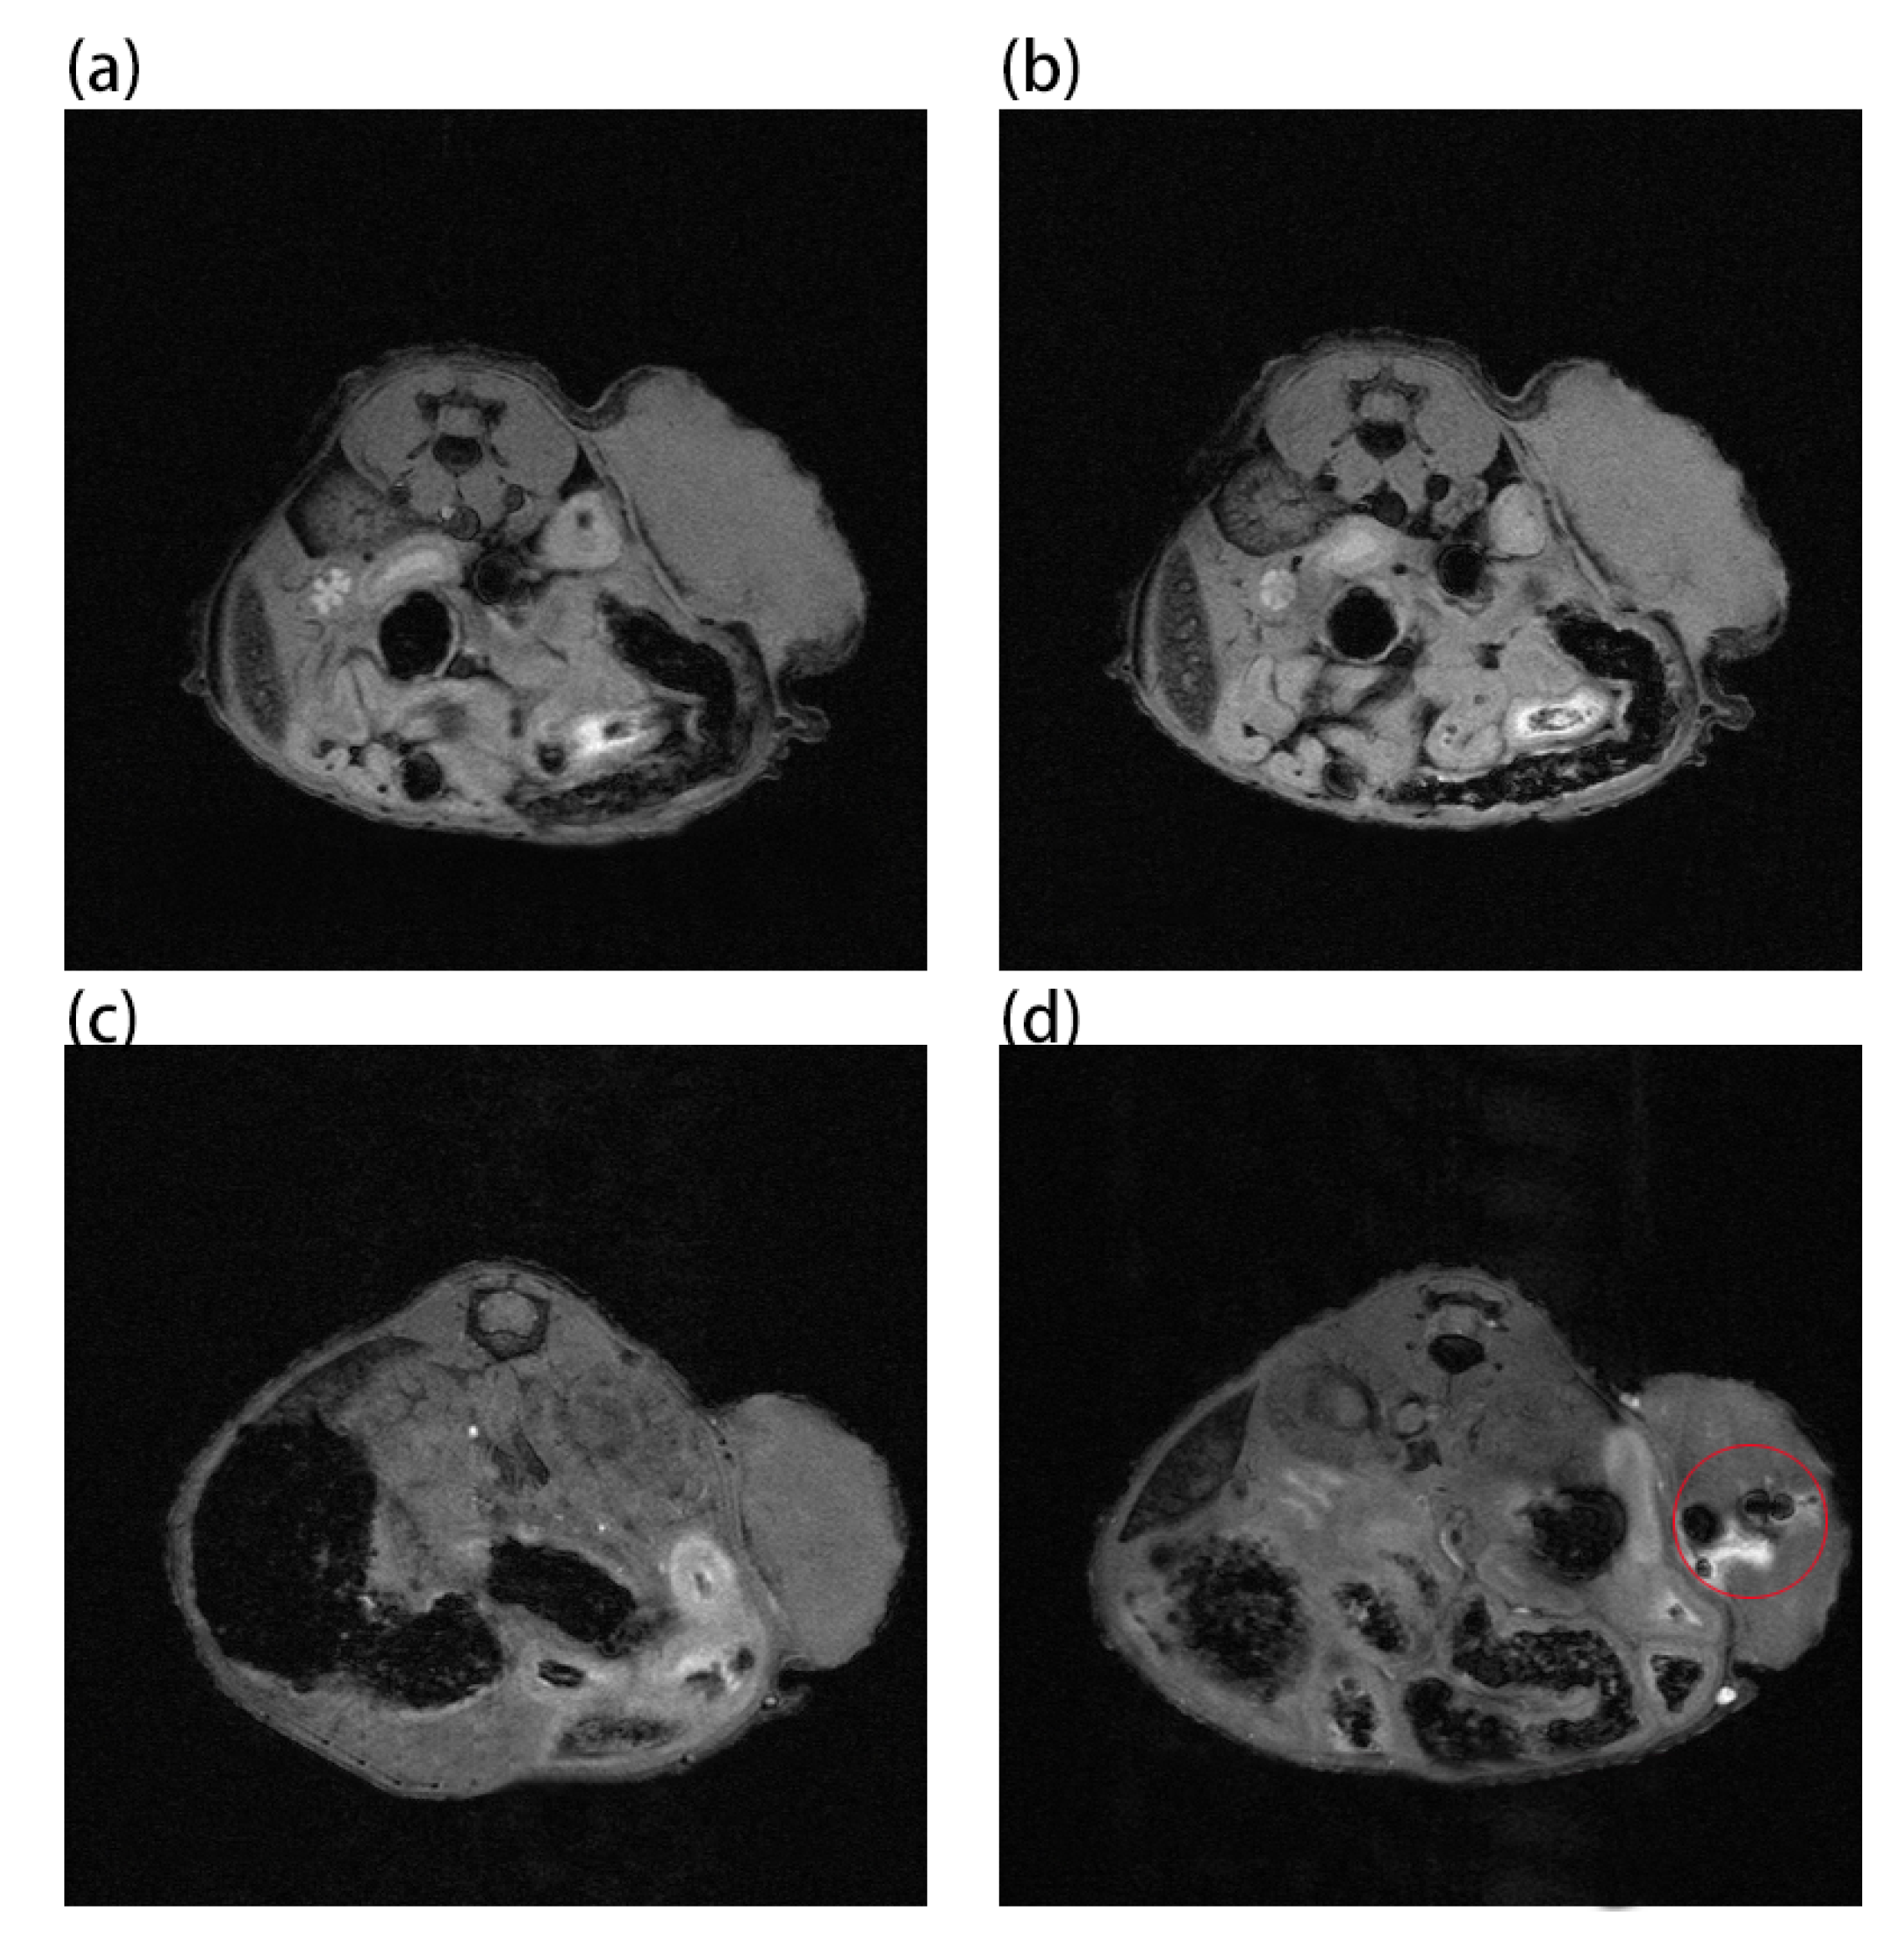

Au and Au-UCNPs-DSPE-PEG2K nanoparticles are injected intravenously into Balb/c mice (Figure 6). As can be seen from Figure 6a,b, there is no difference in MRI images before and after gold nanoparticles injection, demonstrating that gold nanoparticles have no MRI imaging capabilities due to their lack of X-ray attenuation. After injection of Au-UCNPs nanoparticles, obvious MRI signals appear at the tumor location (in the red circle in Figure 6d), which is due to the X-ray attenuation characteristics of UCNPs (Figure S8).

Figure 6. MR images before and after intratumor injection of Au and Au-UCNPs-DSPE-PEG2K in Balb/c mice, (a,b) are before and after injection of Au, (c,d) are before and after injection of Au-UCNPs-DSPE-PEG2K.